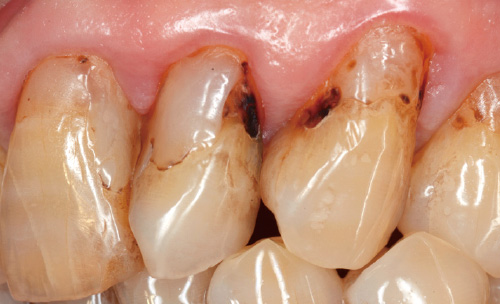

図1:前歯部審美傷害が主訴で来院。失活歯で変色しており大きな窩洞形成も見られ、配列にも歪みがある。

図2:根管治療時にインターナルブリーチを行い、あらかじめ歯の色調コントロールを行った。

図3:2の近心と遠心のⅢ級う蝕に対してアプローチしていく。セレクティブエッチングを行いプライミング、ボンディング、さらにプレカーブの付いたマトリックスを装着。

図4:いかに歯冠外形を回復するかを考えながら、フロアブルCRを充填して側切歯から修復。

図5:残る3本はワックスアップを用いて最終的な歯冠形態を具現化した上で、クリアのシリコンインデックスを採得。

図6:インジェクションテクニックを使って、歯冠形態と審美性の回復を行った。色調は事前にある程度改善しているので、感染歯質と古いCRを除去した。

図7:象牙質とう蝕の深い部分をCRでリベースして、隣在歯はテフロンできちっと隔離した状態でマトリックスを戻してユニバーサルHighフローで充填した。

図8:微妙な形態修正と研磨によって、ほぼダイレクトのクラウンに近いベニアが完成。

図9:従来なら360度削る必要があるケースだが、プレパレーションがかなり難しいケースでもあり、ダイレクトCRによるインジェクションテクニックが適していたと考えている。